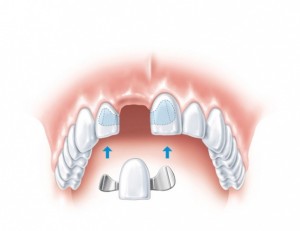

Современная стоматология в городе Сумы предлагает два вида протезирования зубов: съемные, несъемные конструкции.

Если отсутствует большое количество зубов, то протезирование может происходить несколькими способами. Современные способы позволяют решить данный вопрос, пациент никакого дискомфорта не будет испытывать. Современные ортопедические конструкции создают с применением самых новых материалов, а также технологий.